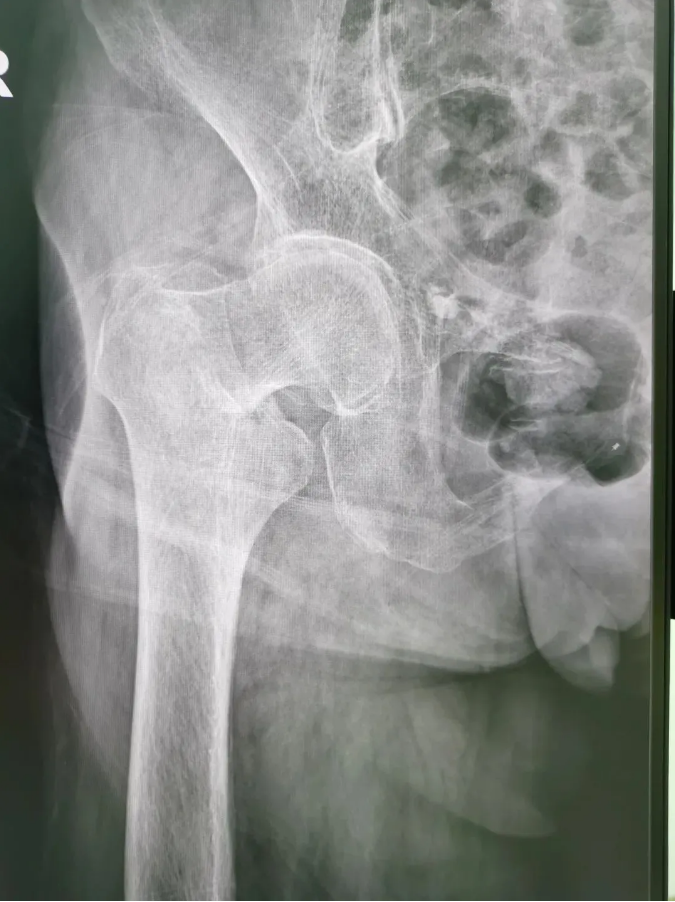

今年91歲的陳婆婆,9月份時在家不慎摔倒,右臀部著地,當下感到髖部劇烈疼痛并活動受限。為求進一步治療,到順德和平外科醫(yī)院骨三區(qū)就診,該區(qū)主任楊升平主任為其診療,被診斷為“右股骨頸骨折”,需進行右股骨頸骨折經(jīng)皮閉合復(fù)位空心螺釘內(nèi)固定手術(shù)。

術(shù)前X光